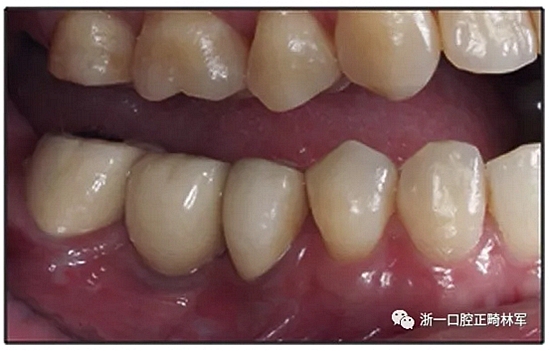

36歲;女性;尋求下頜左后方區(qū)域間隙管理的建議(圖1和圖2),通過(guò)治療獲得了良好的牙頜面效果(圖3和圖4)。她被診斷患有骨性I類(lèi)和代償性牙性II類(lèi)錯(cuò)合畸形,并且上頜左側(cè)尖牙缺失(圖1和2)。大約七年前,由于不可修復(fù)的齲齒,拔除了下頜左側(cè)第一和第二磨牙(圖5)。37相鄰的第三磨牙向近中移動(dòng)并傾斜入間隙,導(dǎo)致無(wú)牙頜間隙減小至約14 mm(圖2和圖5)。臨床和影像學(xué)評(píng)估顯示多發(fā)性齲損和在下頜右側(cè)567處有一不良的固定橋修復(fù)體(圖1和5)。此外,下頜左中切牙缺失,造成下頜中線(xiàn)向左側(cè)偏移約3 mm(圖1和圖2)?;颊咦栽V,她的右上第一前磨牙和左上尖牙在13歲時(shí)由其家庭牙醫(yī)拔除,因?yàn)樗鼈儽蛔枞筋a側(cè)萌出(圖1)。上頜第二磨牙缺失(未知病因),并且相鄰的第三磨牙已經(jīng)轉(zhuǎn)移到第二磨牙間隙中。如補(bǔ)充材料所示,美國(guó)正畸學(xué)差異指數(shù)DI是28分。種植體部位(下頜左側(cè)和右側(cè)第一磨牙)由于復(fù)雜性得到額外4分(補(bǔ)充材料)。

圖1. 治療前面部和口內(nèi)照片